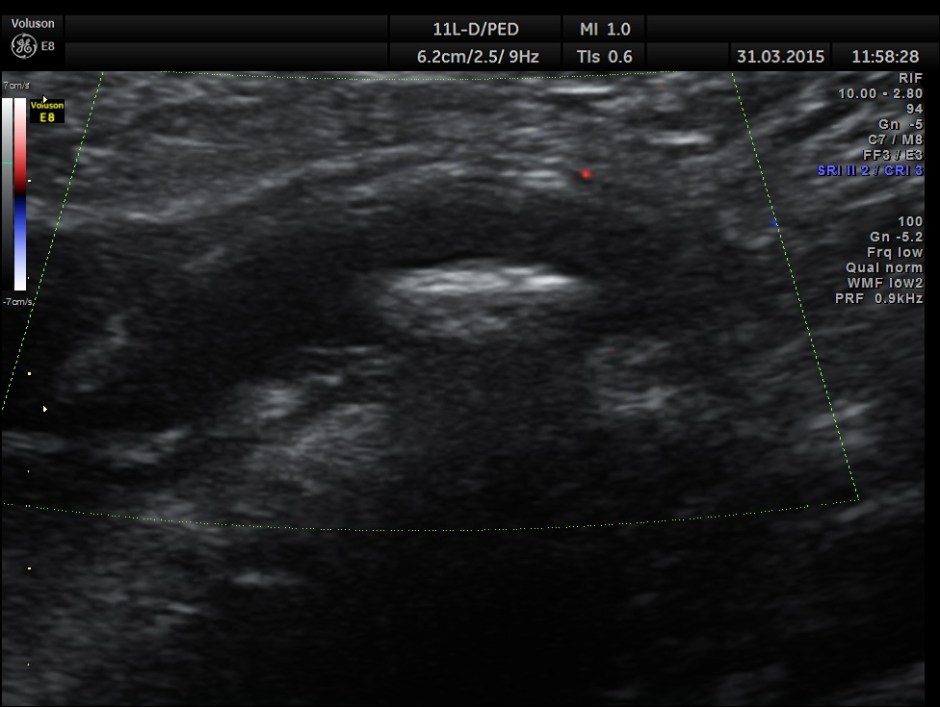

The following pictures are with a high resolution probe.

The following picture shows the long and short axis views.

Careful attempt to establish any continuity of the dilated ” tube ” to the ureter or dilated pelvis , showed that the dilated structure was separate from the right ureter .